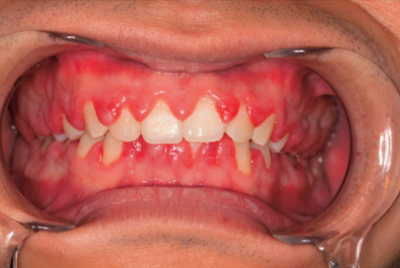

32歳の男性。歯肉の腫脹と出血を主訴として来院した。数日前から微熱と倦怠感を自覚しているという。初診時の口腔内写真を別に示す。血液検査結果を表に示す。